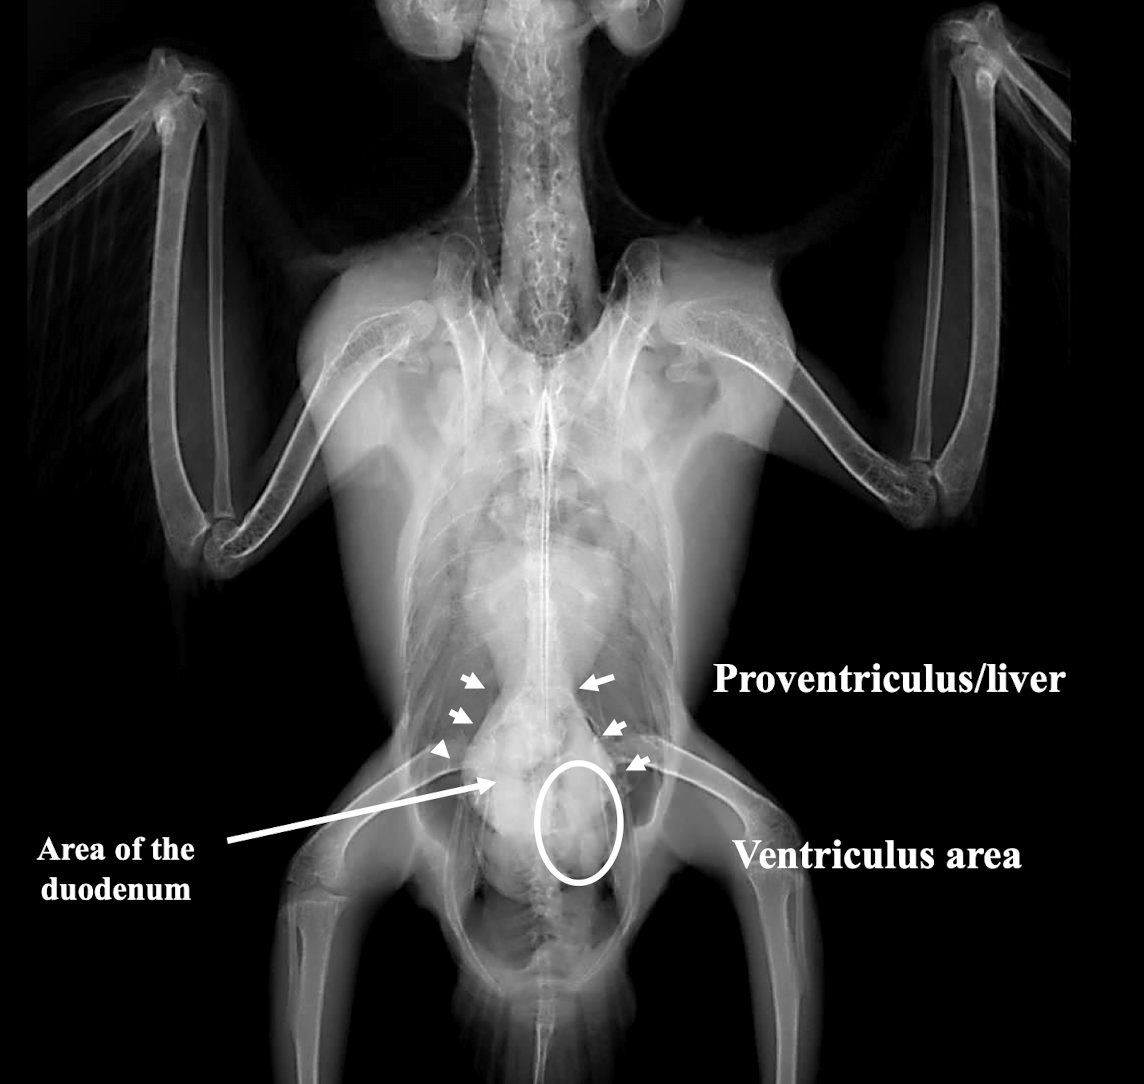

GI tract

When are barium studies indicated in birds?

To localize the GI tract, assess hypomotility, identify obstruction/occlusion, or evaluate changes in location/shape of other organs.

Proventricular Dilation and metal/grit in the ventriculus.

What is wrong?

Proventricular dilation

metal/grit in ventriculus